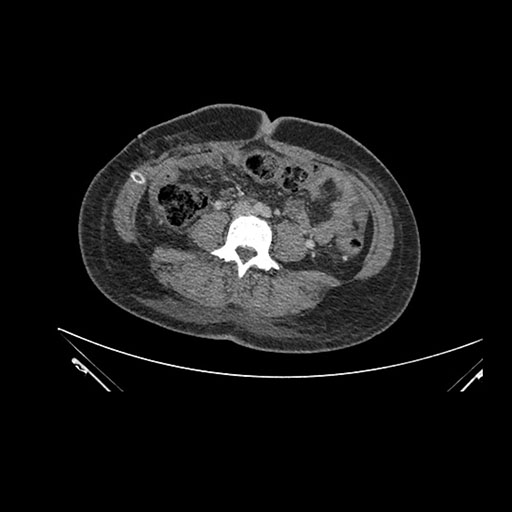

Imaging Analysis

Look through the patient's CT scan to identify any areas of concern for the necessary procedure.

Axial Venous

Based on initial findings, which issue(s) would you be most concerned about?